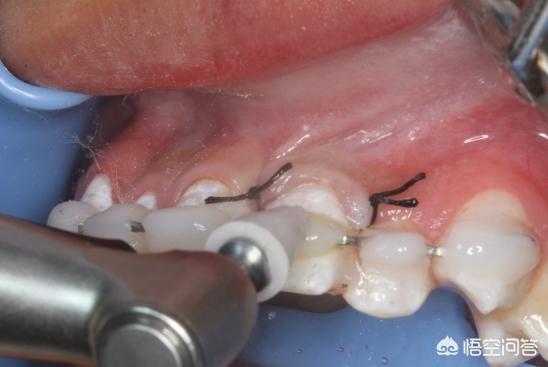

2,手术治疗:顽固的牙周问题需要进行牙周手术治疗(牙周翻瓣手术)并配合药物治疗。经过上述治疗后,大多数患者的牙周炎症可得到消除,松动牙齿得以稳固。

1、清除致病菌第一步牙周基础治疗,先超声波洗牙清除牙龈上的牙结石,如果牙齿松动就得牙周夹板固定,第二步再用刮治器刮除牙龈下的牙结石,最后清洗上药消毒。

2、像慢性牙周病还得测量牙周袋深度,可能得切掉部分受感染的肉芽组织,再将牙龈进行缝补,促进牙周组织愈合,另外得控制病理性牙齿松动移位,牙龈恢复一段时间后多按摩,增强牙龈组织抗病能力。